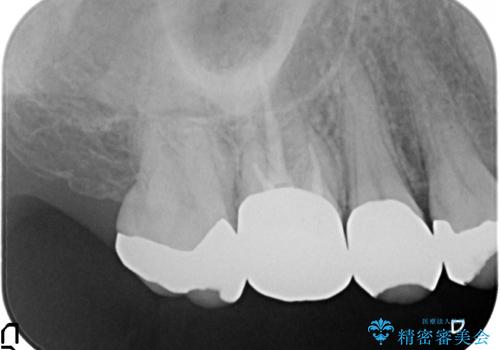

- ものを咬むと右上の歯が痛むといらっしゃった方の症例です。

検査の結果右上5の歯の神経が死んでいたため、根管治療を行った後に、オールセラミッククラウンによる補綴を行いました。

また右上6に関しては再根管治療を行い、右上4に関しては虫歯治療を行った後に、オールセラミッククラウンによる補綴を行いました。